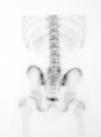

A los 15 días el paciente se presenta con sintomatología atenuada. La GOP/SPECT (figs. 4 y 5) demuestra fenómenos de remodelación ósea a nivel de ambas pars de L5. Por tanto, se concluye el diagnóstico de espondilólisis activa L5 derecha y espondilólisis izquierda en formación. Se continúa el mismo tratamiento agregándose una pauta específica de ejercicios delordosantes y ortesis plantares de corrección.

Figura 4

Figura 5